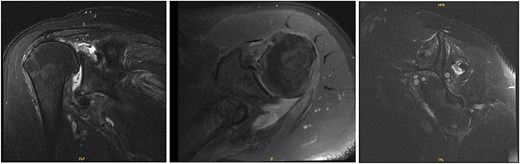

At 2-week follow-up, he reported continued shoulder pain. His right-sided paresthesias had resolved; however, he reported continued paresthesias into his left forearm and hand. He had significant bilateral limitation in range of motion, and weakness on internal and external rotation, more so on the left. Special tests included a positive Jobe test, drop arm test, belly press test, Obrien’s test, and Speed’s test bilaterally, as well as a positive left-sided bear hug test. He was advised to start gentle range of motion, avoid lifting, and was sent for bilateral shoulder MRIs (Figs 5 and 6).

MRI of the right shoulder demonstrating full-thickness tearing of the supraspinatus and infraspinatus with medial tendon retraction, a high riding humeral head, intermediate grade partial thickness tear of the teres minor, severe fatty atrophy of the subscapularis muscle belly, labral degeneration, and tearing, partial thickness tearing of the inferior glenohumeral ligament, anterior-inferior glenoid subchondral marrow edema, and severe glenohumeral cartilage abnormalities.

MRI of the left shoulder demonstrating a full-thickness tear of the supraspinatus and infraspinatus with tendon retraction, high grade partial thickness tearing of the subscapularis, full-thickness tear of the biceps long head tendon, complex anterior labrum tear, partial thickness tear of the inferior glenohumeral ligament including the anterior and posterior bands, inferior glenoid subchondral marrow edema, and moderate glenohumeral degenerative changes.